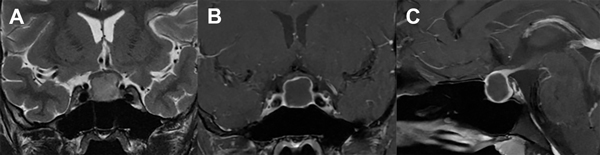

Paciente de sexo masculino de 17 años de edad, sin antecedentes de relevancia, que consultó a la guardia del hospital por presentar fiebre, cefalea intensa y vómitos de 48 horas de evolución. Al examen neurológico se encontraba lúcido, sin alteración de pares craneales, sin déficit motor ni sensitivo y presentaba rigidez de nuca. Se interpretó el cuadro como un síndrome meníngeo, por lo que se realizó un análisis de sangre que evidenció leucocitosis leve, una tomografía computada (TC) de encéfalo informada como normal y una punción lumbar. El examen físico-químico del LCR evidenció un color cristal de roca, 1425 células/mm3 con predominio mononuclear, glucorraquia de 53 mg/dl (glucemia de 102 mg/dl) y proteínas de 110 mg/dl, interpretándose como una meningitis, iniciándose tratamiento antibiótico y antiviral empírico. La serología para HIV y VDRL fueron negativas. Los cultivos de LCR fueron negativos para gérmenes comunes, micobacterias y hongos, así como también el panel viral, por lo que se interpretó como una meningitis aséptica. Se completó estudio con imagen por resonancia magnética (IRM) de encéfalo que evidenció una lesión expansiva selar con extensión supraselar de 14 x 16 mm de diámetro, quística, hipointensa en T1, levemente hiperintensa en T2, sin restricción en secuencia de difusión, con refuerzo periférico tras el contraste, con compresión y deformidad del quiasma óptico (Fig. 1). Tras este hallazgo, se realizó un campo visual computarizado que fue normal y se plantearon diferentes diagnósticos diferenciales: quiste de la bolsa de Rathke, craneofaringioma y adenoma quístico. El panel hormonal no evidenció alteración de la función hipofisaria y el paciente no refería trastornos en el crecimiento, ni en la libido, ni tampoco signosintomatología de diabetes insípida u otra alteración hidroelectrolítica. Tampoco se evidenciaron calcificaciones de la lesión en la TC. Se discutió el caso y se decidió la conducta quirúrgica.

Figura 1. A: IRM T2 coronal en la que se visualiza tumor selar con desplazamiento del quiasma óptico. B y C: IRM T1 coronal y sagital con gadolinio que muestran centro hipointenso con captación periférica en anillo.